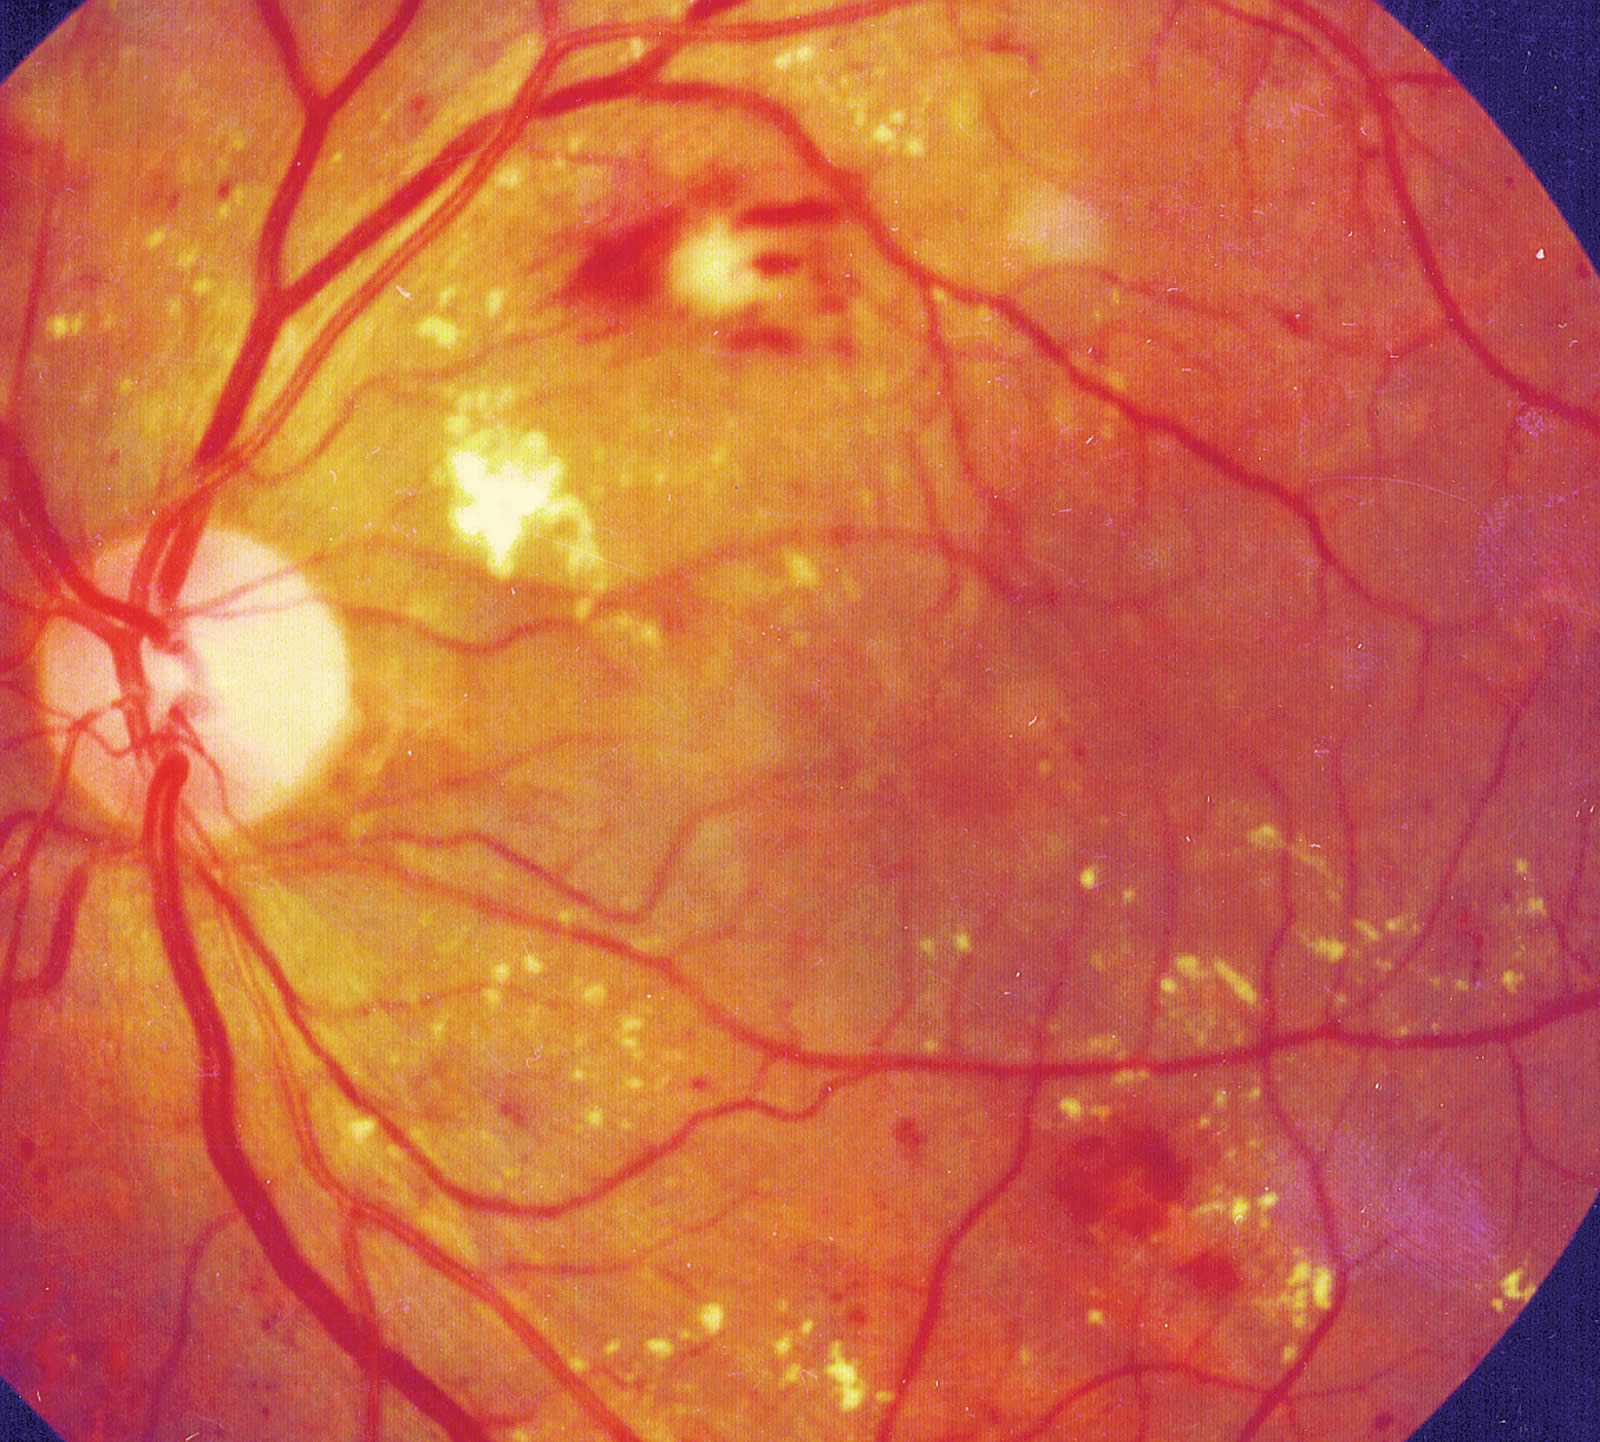

The following photographs show non-proliferative and macular diabetic retinopathy.

- Moderate non-proliferative diabetic retinopathy (Figure 1).

The lesions in the retina at this stage are within the retina and include micro-aneurysms, small ‘dot and blot’ haemorrhages, ‘splinter’ haemorrhages, intraretinal microvascular abnormalities (IRMA) and ‘cotton wool’ spots.

The presence of these lesions in various degrees determines whether the NPDR is ‘mild’, ‘moderate’, ‘severe’ and ‘very severe’.

2. Moderate non-proliferative diabetic retinopathy

Intraretinal microaneurysms and dot and blot haemorrhages of greater severity, in one to three quadrants. Cotton wool spots, venous calibre changes including venous beading, and intraretinal microvascular abnormalities are present but mild.